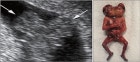

2. 다태임신서 융모막성과 자궁경부길이 측정의 중요성

여러 가지 이유가 있지만 연예인 송일국씨가 나왔던 ‘슈퍼맨이 돌아왔다’의 삼둥이도 아주 큰 몫을 한 것으로 보인다. 일반적으로 생각해도 다태임신은 매우 힘들고, 산모, 태아 모두에게 위험하다. 따라서...  [의학신문 2016-04-19 16:16:00]